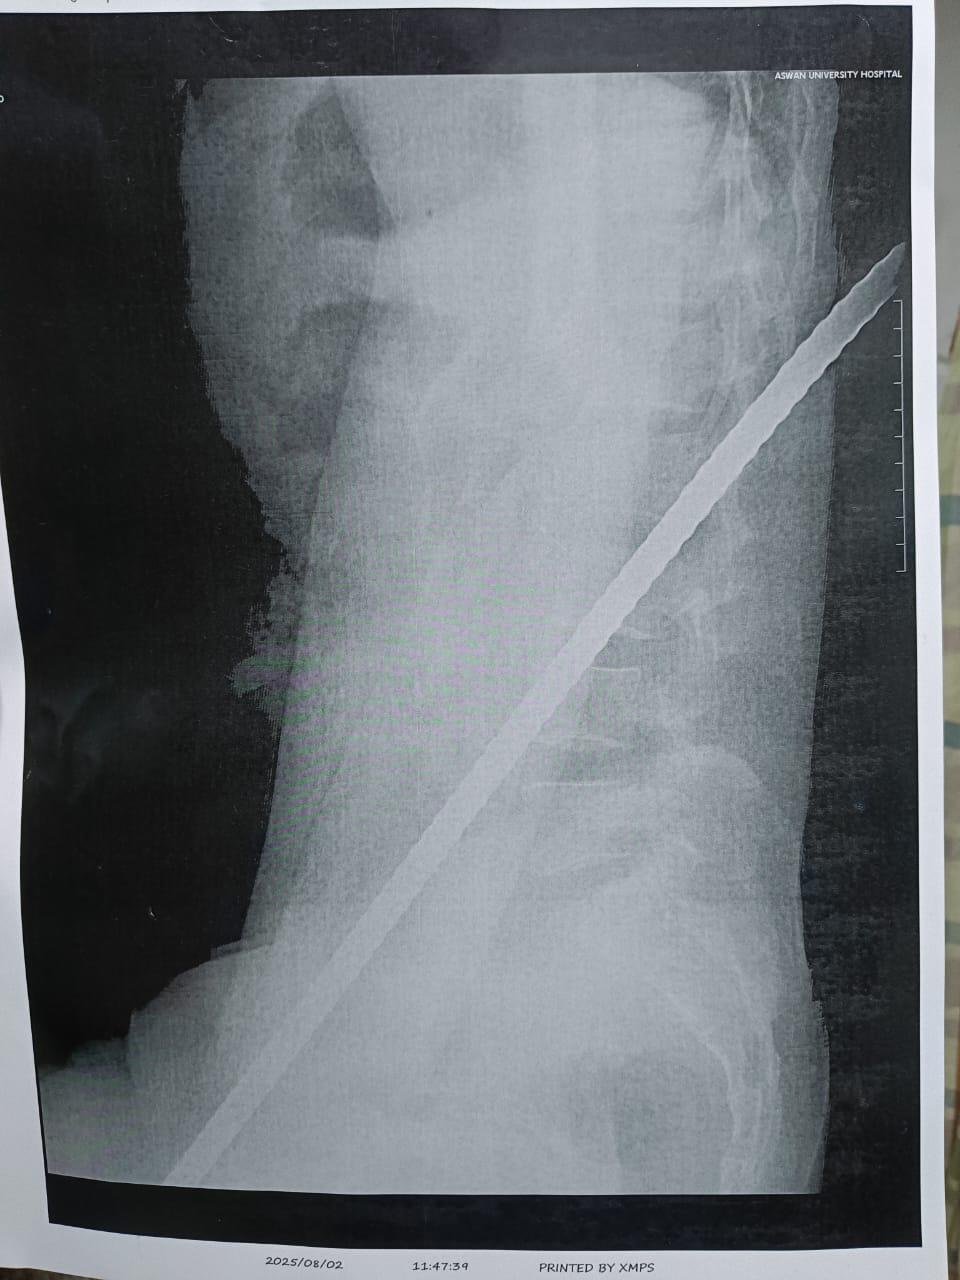

أطباء مستشفى أسوان الجامعي ينقذون حياة مريض بعد اختراق سيخ حديدي لظهره وكليته (صور)

نجح فريق طبي متخصص بمستشفى أسوان الجامعي، في إنقاذ حياة مريض يبلغ من العمر 33 عامًا، مصابا باختراق سيخ حديدي لمنطقة الظهر والكُلية اليسرى، وذلك عقب سقوطه من الطابق الثالث بإحدى البنايات السكنية.

استقبلت طوارئ المستشفى الجامعي المصاب وهو في حالة حرجة، وتم إجراء الفحوصات اللازمة وتبين أن السيخ اخترق الظهر والكلية وخرج من الناحية المقابلة، ما تسبب في تهتك بالأمعاء وانشطار جزئي بالكُلية اليسرى.

وتمكن الفريق من استخراج السيخ الحديدي، مع إصلاح الكُلية المتضررة وتفادي استئصالها، بالرغم من وجود نزيف حاد وخطورة شديدة في الإصابة، فيما استقرت حالة المريض وخرج من غرفة العمليات في وضع صحي جيد.